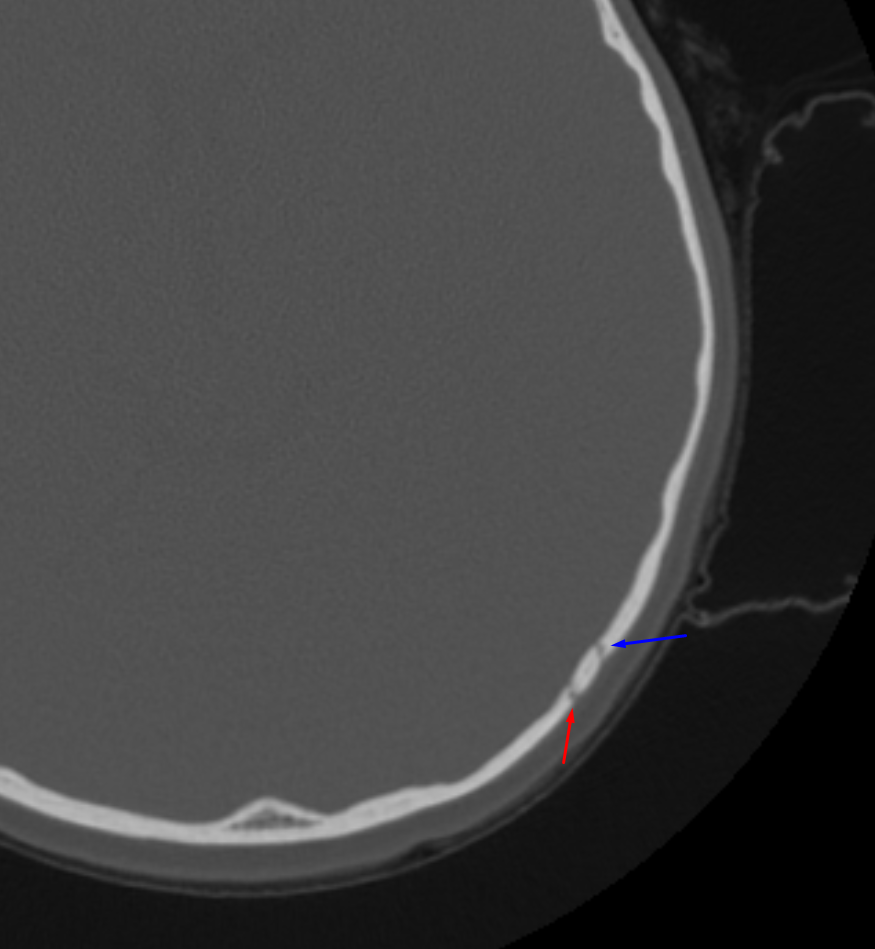

Age: 4

Sex: Female

Indication: MVC